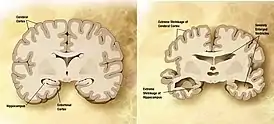

![]() Мозг пожилого человека в норме (слева) и при патологии, вызванной болезнью Альцгеймера (справа), с указанием отличий. | |

Болезнь характеризуется потерей нейронов и синаптических связей в коре головного мозга и определённых субкортикальных областях. Гибель клеток приводит к выраженной атрофии поражённых участков, в том числе к дегенерации височных и теменной долей, участков фронтальной коры и поясной извилины[68].

Как амилоидные бляшки, так и нейрофибриллярные клубки хорошо заметны под микроскопом при посмертном анализе образцов мозга больных[12]. Бляшки представляют собой плотные, в большинстве случаев нерастворимые отложения бета-амилоида и клеточного материала внутри и снаружи нейронов. Внутри нервных клеток они растут, образуя нерастворимые закрученные сплетения волокон, часто называемые клубками. У многих пожилых людей в мозге образуется некоторое количество бляшек и клубков, однако при болезни Альцгеймера их больше в определённых участках мозга, таких как височные доли[94].